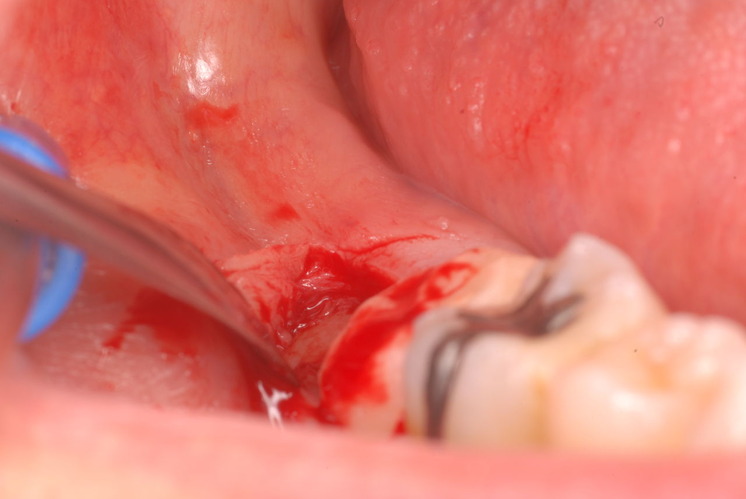

下記は患者に言われるままに血だらけでの不潔な状態で虫歯をとり埋めたようで全然適合していませんし、外れそうになっていました。

外したところです。中は虫歯のオンパレードでした。